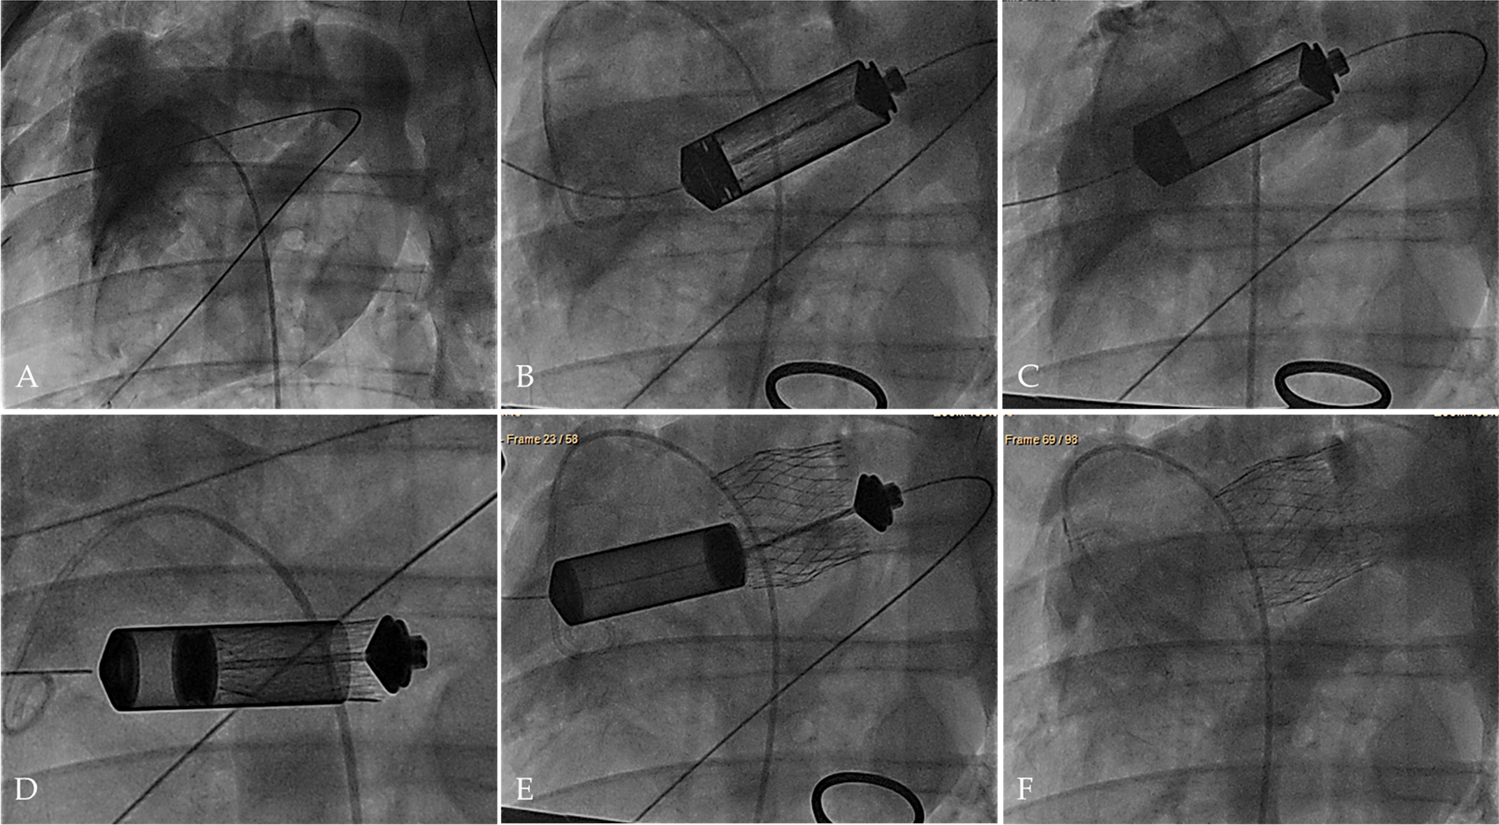

Fig. 4

Transapical hTESV delivery under fluoroscopy guidance. a Imaging of the native pulmonary root. b, c Insertion and alignment of the delivery system to the implantation site. d, e Controlled positioning and deployment of the hTESV. f Final evaluation of the deployed hTESV confirming sufficient positioning and good valve functionality